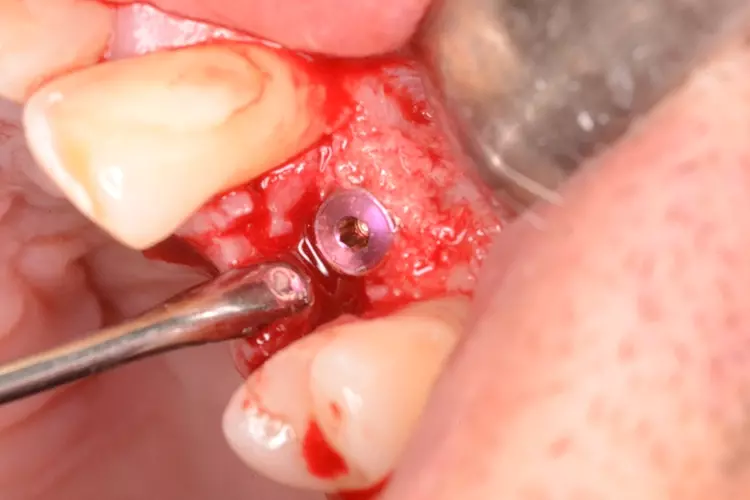

Bei dem heute 49-jährigen Patienten wurde seit Kindertagen versäumt, die Ober- und Unterkieferzahnbögen kieferorthopädisch auszurichten. Der Patient leidet seitdem stark unter seinen Zahnfehlstellungen.

Die Fraktur des stark elongierten Zahnes 21 war für den Patienten der Ausgangspunkt, sowohl die Front des Ober- als auch des Unterkiefers prothetisch überarbeiten zu lassen. Dabei wurde der frakturierte Zahn 21 durch ein navigiert eingesetztes Sofortimplantat ersetzt, während die verschachtelt stehenden Zähne 12 und 42 durch eine Brückenversorgung korrigiert wurden (Abb. 4a-j).